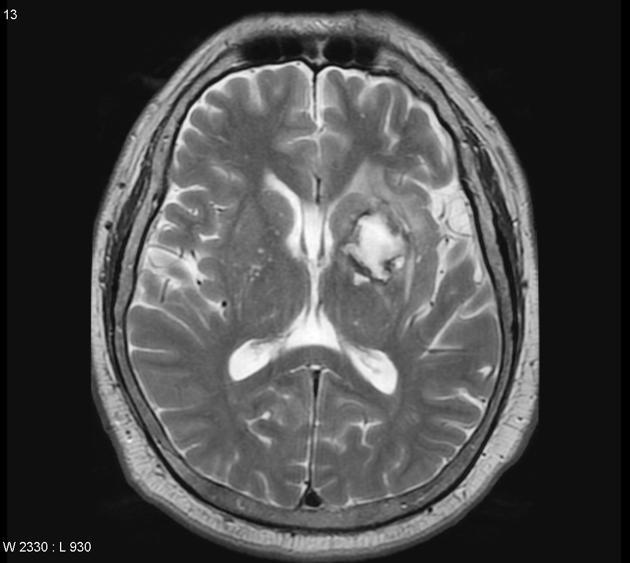

В режиме Т2 определяется гиперинтенсивный сигнал от опухоли, с неоднородной структурой, участками некроза и отёка.

В режиме с контрастированием определяется усиление в активной части опухоли, отсутствие усиления в зонах некроза.

- Опухолевые поражения визуализируются в Т1 с контрастированием и в Т2, определяется структура, васкуляризация, зоны некроза, инфильтрации и распространение.